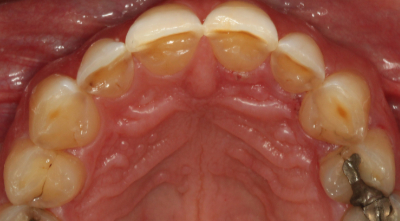

二次元評価から、咬合不安定性の徴候は明らかでした。 ダレンは、切歯縁が非常に薄く、欠け、透明になりつつあるほどでした。 上顎前歯の舌側にはほとんど棚が装着されており、機能的な包絡線が制限されていることが示唆されました。 また、前歯だけでなく後歯にも象牙質への摩耗があり、前歯はクラス1の可動性を持っていました。

LUCKY.LUCKY.LUCKY.LUCKY.LUCKY.LUCKY.LUCKY.LUCKY.LUCKY.LUCKY.LUCKY, この患者はPiper TMJ Classification 1で、健康な無傷の関節アセンブリでした。 彼の機能的な問題は主に咬合筋でした。 しかし、歯列は胃食道逆流症(GERD)を示唆するプレゼンテーションで酸腐食の兆候を示したので、我々はダレンを主治医に紹介し、歯科治療を始める前にGERDの治療を受けました。

審美的には、彼の上顎切歯縁はわずかに垂直方向に欠損しており長さを伸ばす必要がありました。 ダレンは咬合平面がわずかにカントしていましたが、本人はその矯正には興味がありませんでした。 下顎切歯面やアーチフォームも改善が必要でした。